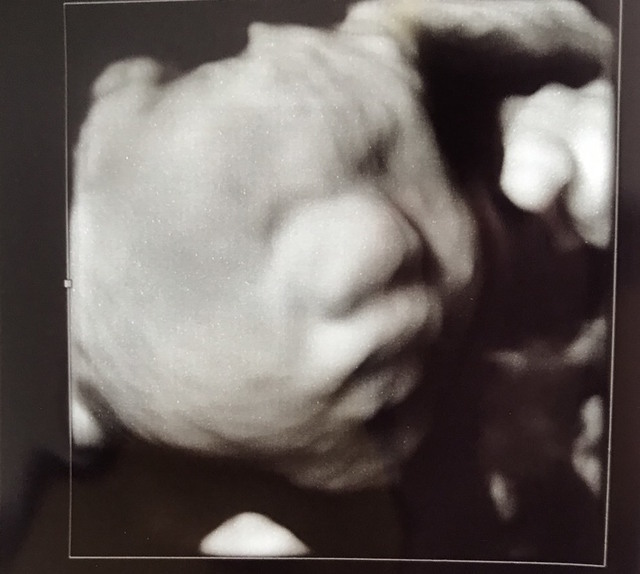

29週4日(29w4d・男の子)|Ri0118 さん(30歳)

エコー写真撮影時のエピソード:

逆子で4D撮影は無理かなぁ?って先生の判断でしたが、諦めきれず少し時間を置いてまた撮ってもらうことになりました。

数分で逆子が治ることも無く、ショックを受けていたら先生が 「逆子治してみるか!」って急なヒラメキでお腹の上からグッ!って押して逆子を治してくれました。

赤ちゃんはくるっと回って、しばらくビックリしてシャックリしていましたが、落ち着いたのか腕枕ですやすやしている写真が撮れました!